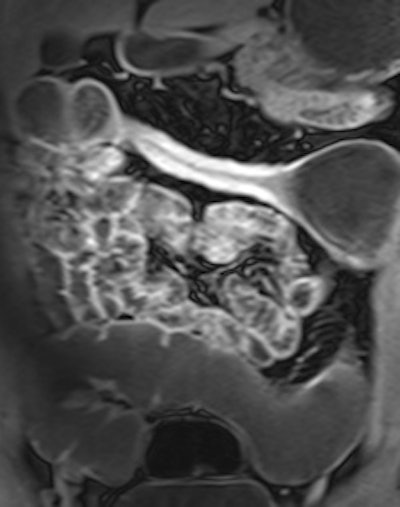

MRE can distinguish between inflammatory, stricturing and penetrating disease, and can be performed prior to video capsule endoscopy (VCE) in excluding strictures where VCE can then be used to detect subtle mucosal disease. In combination with blood and fecal biomarkers and endoscopy, MRE can assist the treating clinician in distinguishing between inflammatory stenoses amenable to medical therapy and fibrostenotic disease requiring surgery, she wrote in an article published online on 16 March by Insights into Imaging.

MRE is a particularly useful in the assessment of treatment response. When MRI is performed during an acute relapse and then in remission, a reduction in both mural contrast enhancement and in mural thickness in affected segments is seen, but luminal stenosis may persist. Biologics such as infliximab and adalimumab have been used to treat patients with Crohn's disease resistant to other therapies with mucosal healing as a key treatment goal.

"From our experience, MRE can be used to show a significant reduction in inflammatory activity (as demonstrated by reduced mural thickening, edema, and enhancement) following treatment with such agents. DWI may have a role in response assessment with a predicted decrease in the degree of restricted diffusion. However, as yet there are no published papers on this subject," explained Griffin.